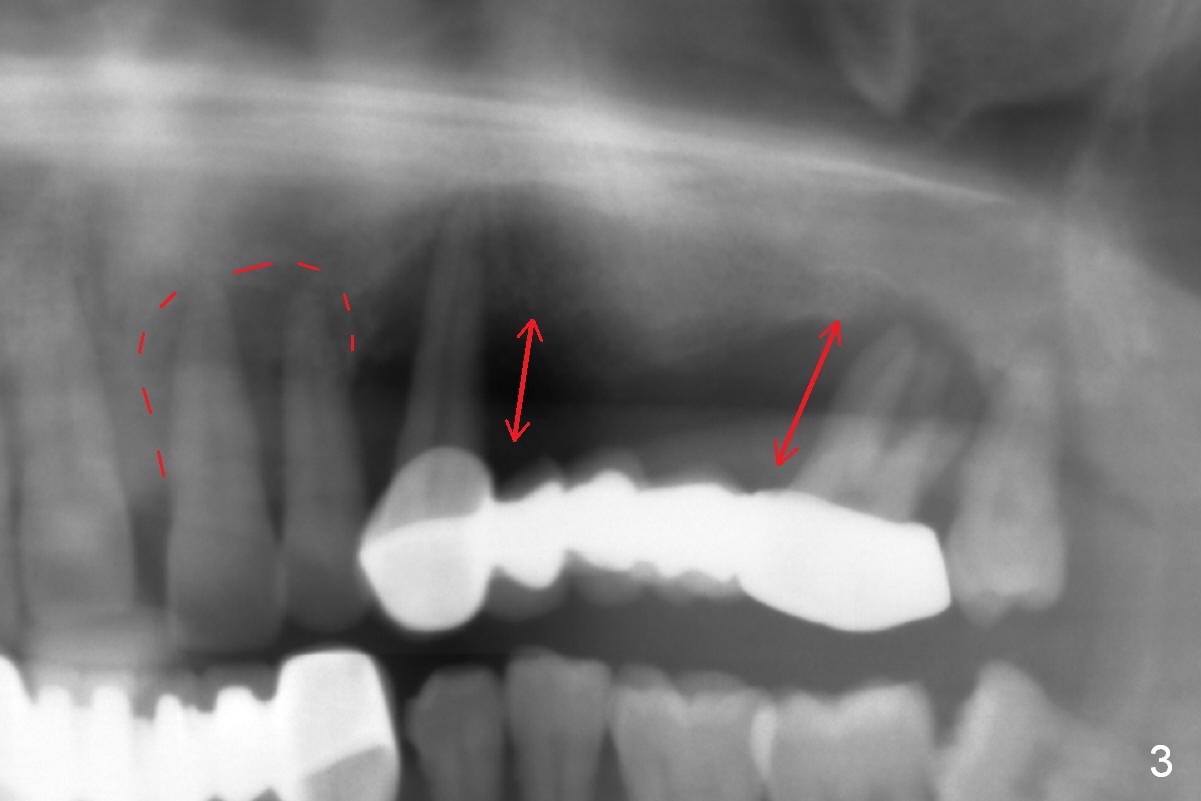

In addition to the large radiolucency around the roots of #9 and 10 (Fig.3 red dashed line), the gingiva at #11 and 15 is excessively thick (red arrows).